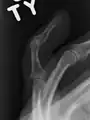

X-ray showing fracture at the insertion of the extensor tendon X-ray showing fracture at the insertion of the extensor tendon

A mallet finger usually results from overbending of the finger tip.[3] Typically this occurs when a ball hits an outstretched finger and jams it.[3] This results in either a tear of the tendon or the tendon pulling off a bit of bone.[3] The diagnosis is generally based on symptoms and supported by X-rays.[3]

The diagnosis is generally based on symptoms and supported by X-rays.[3] The injury can be accompanied by swelling and ecchymosis.[4]